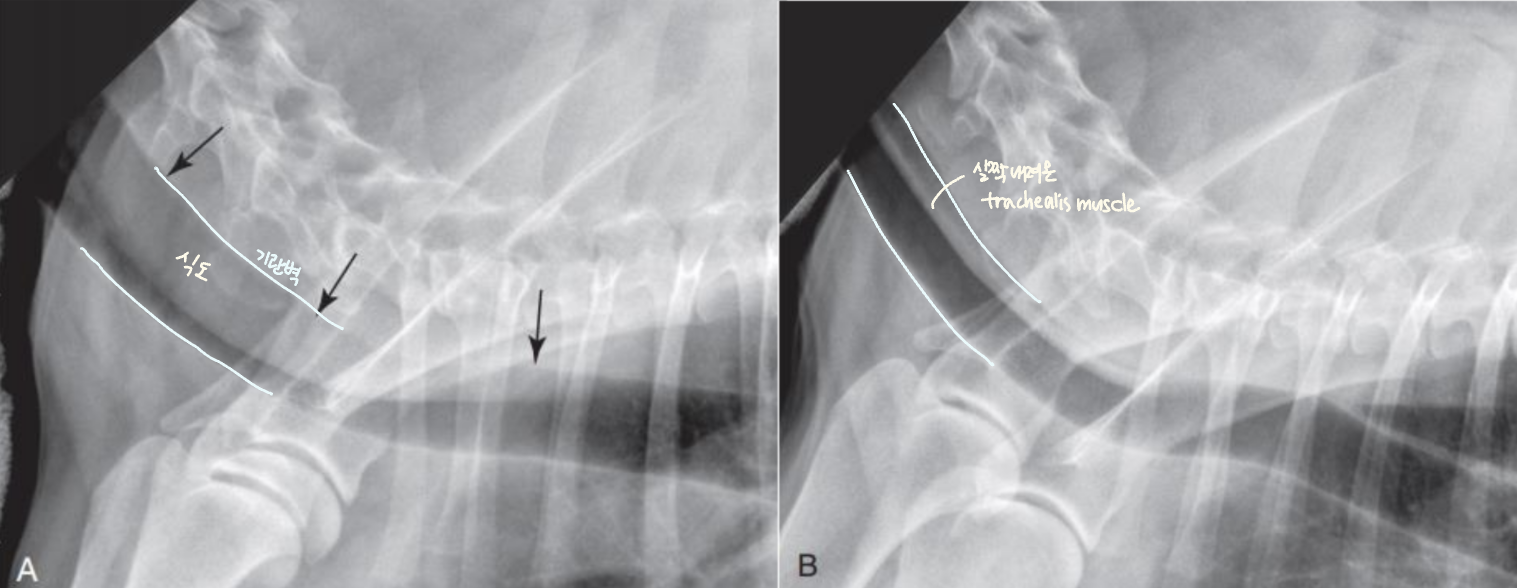

Tracheal diameter 재는 법법

• Thoracic inlet과의 비율로 나타낸다.

- T1의 끝부분에서, 1번 sternum의 가장 오목한 부분 (Thoracic inlet)을 선으로 잇고 길이를 잰다.

- Trachea의 길이를 잰다.

- 비율은 보통 0.2 정도.

(단두종에서는 정상적으로 더 작다.)

Static : 주기 상관없이 계속 무너져 있음

Dynamic : 호기/흡기에 따라 달라짐

많이 무너지는 위치

Cervical : 흡기에는 경추 쪽이 많이 무너짐 (thoracic inlet)

Intrathoracic : 호기에는 흉강 압력이 증가하여 흉강 쪽이 무너짐